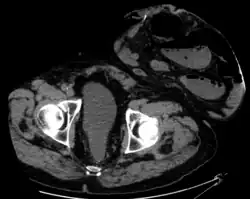

Parastomal hernia is the most common late complication of stomata through the abdominal wall, occurring in 10 to 25% of the patients.[1]

One well-known form of an artificial stoma is a colostomy, which is a surgically created opening in the large intestine that allows the removal of feces out of the body, bypassing the rectum, to drain into a pouch or other collection device. This surgical procedure is invoked usually as a result of and solution to disease in the GIT. The procedure involves bisecting this tube, usually between the later stage of the small intestine (ileum) and the large intestine or colon, hence colostomy, and exiting it from the body in the abdominal region. The point of exiting is what is known as the stoma.

For greatest success and to minimize negative effects, it is preferable to perform this procedure as low down in the tract as possible, as this allows the maximal amount of natural digestion to occur before eliminating fecal matter from the body. The stoma is usually covered with a removable pouching system (adhesive or mechanical) that collects and contains the output for later disposal. Modern pouching systems enable most individuals to resume normal activities and lifestyles after surgery, often with no outward physical evidence of the stoma or its pouching system.